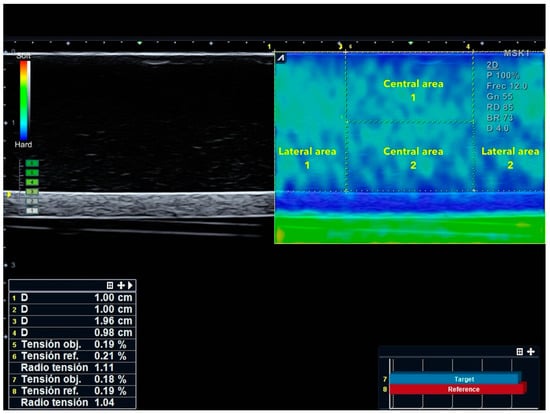

Once captured, all the images were assessed using offline measurement tools of the US equipment to calculate the SR. Relative SRs were calculated as the stiffness of the reference area divided by the stiffness of the comparator area. Two different SRs were calculated as follows (Figure 2):

Figure 2.

Strain ratio (SR) calculation of lateral and central areas. Central area 1 (reference) was compared with Central area 2 (target). Lateral area 1 (reference) was compared with Lateral area 2 (target).

- Lateral areas of the image: First, the caliper was used to measure 1 cm from the top right corner of the image to the left. Then the area selector tool was utilized to contour a rectangle with 1 cm width and a height equal to the distance between the most superficial limit of the phantom to the most superficial limit of the cylindrical structure. Finally, another rectangle with same measurements (height and width) was placed in the top left corner of the image to obtain the SR.

- Central areas of the image: Within the central 2 cm that were not included in the previous measurement, the distance from the surface of the phantom and the upper limit of the cylindrical structure was divided by 2. Following this, a rectangle was contoured with a width of 2 cm and the upper half of the distance previously calculated from the surface to the fake vessel. Finally, the SR between the upper rectangle and the lower rectangle was calculated.